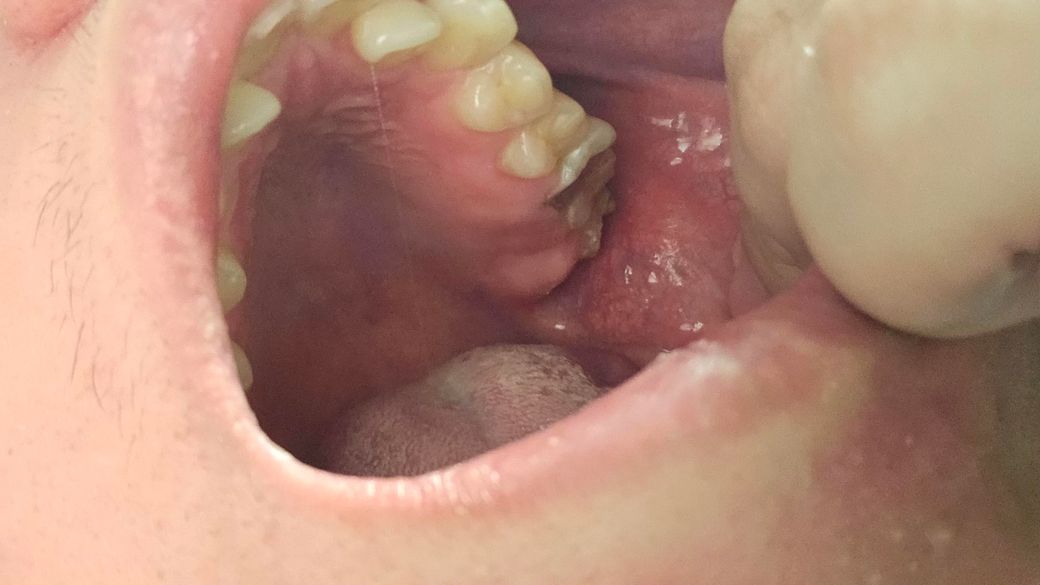

제가 6월아니면 7월에 치과 갔는데요 조금 늦게 갔는것가요? 이쪽 이빨 이상태인데요

• 1번 째 사진

사진상으로 치아가 깨진것처럼 보입니다 치아가 깨졋거나 충치가 진행된 상태라면 최대한 빨리 가시는게 좋습니다.

치아의 많은 부분이 충치로 인해서 손상된것으로 보입니다. 빠른 치료가 필요할거으로 보이며 충치가 치아의뿌리까지 진행이 되었다면발치를 해야 할수 있습니다.

사진상 보이는 어금니의 경우 충치가 깊어보여서 신경치료 등 치료보다는 발치가능성 높습니다